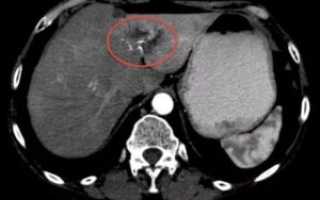

Все объемные новообразования, определяемые при проведении компьютерной томографии, разделяют в зависимости от ряда параметров: плотность, структура, форма, контуры, размер, локализация.

Плотность – это основная характеристика любой ткани, измеряется на компьютерной томографии в единицах Хаунсфилда. По плотности бывают очаги гиподенсивные, гиперденсивные, изоденсные. По показателю плотности есть основания предполагать, что находится в структуре очага, присутствует ли жидкость, кровь, мягкотканные компоненты.

Что такое гиподенсивность, когда она проявляется

Под термином гиподенсивность необходимо понимать снижение плотности тканей печени. Каждая ткань человеческого организма отличается определенной плотностью, что видно на томографических и рентгеновских снимках. При патологиях печени структура органа становится неоднородного цвета, присутствуют затемненные участки. Обнаружение такого очага говорит о развитии заболевания.

Подобные изменения плотности могут быть симптомом любой патологии, от доброкачественных новообразований и до опасных для жизни злокачественных опухолей с метастазами. В ряде случаев гиподенсивные образования обусловлены наличием врожденных патологий.